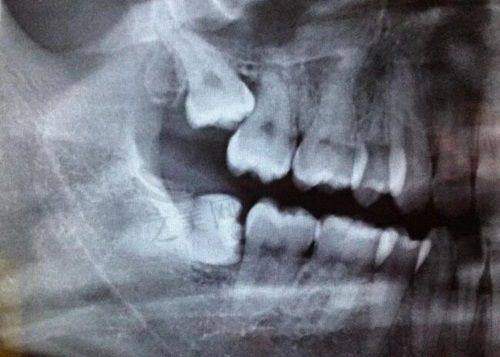

当错颌畸形重度,还伴随颌骨畸形,或者是在成年时期进行矫正时,颌骨改建较慢,矫正时间长,容易反弹,会出现牙齿移动等现象,这种情况下可能需要终身佩戴保持器来维持牙齿在颌骨的位置。像骨性的地包天、龅牙、开颌、偏颌等情况也可能需要终身佩戴。特定的矫治病例,如扩弓矫治、下颌扩弓、存在多个散在间隙、成人重度唇舌向错位牙矫治后以及上颌中切牙间隙关闭等病例,通常需要终身佩戴保持器以防止畸形复发。复杂矫正病例,如牙齿间隙较多或原始牙列拥挤重度的情况,保持器的使用时间通常会延长,甚至可能需要终身佩戴。